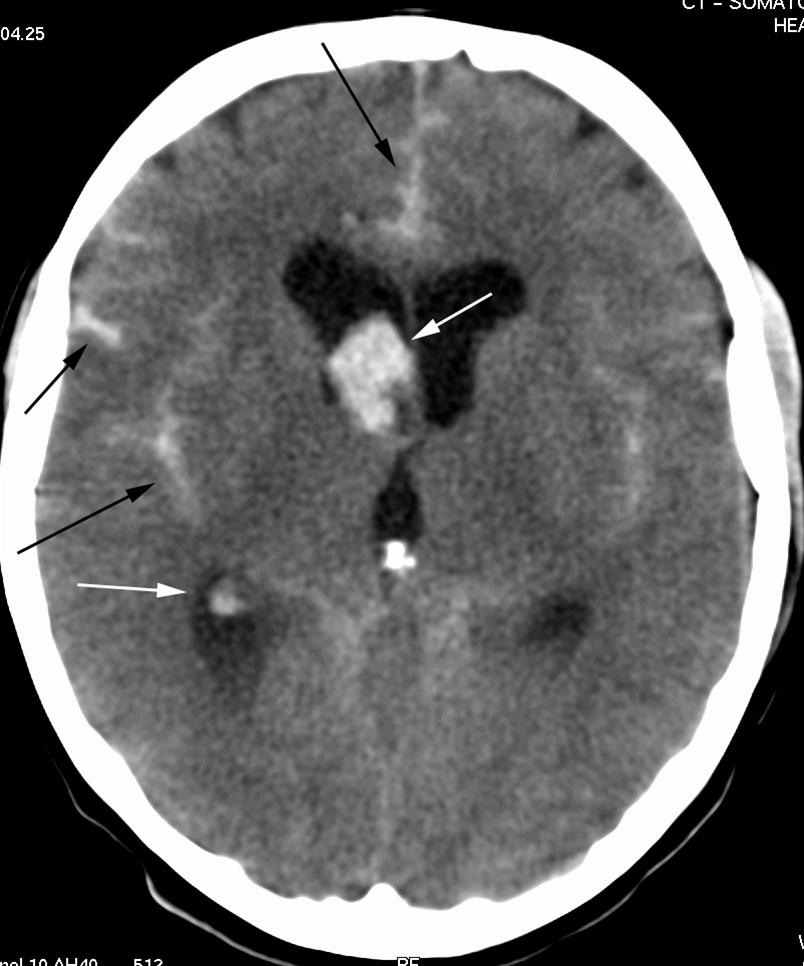

CT skanning af hjernen (axialbillede) uden kontrast.

Blod (lyse områder) i højre sideventrikel (hvide pile), mellem hemisfærerne frontalt og i fissura Sylvii på begge sider (sorte pile). Kalk i corpus pineale (intenst hvid).